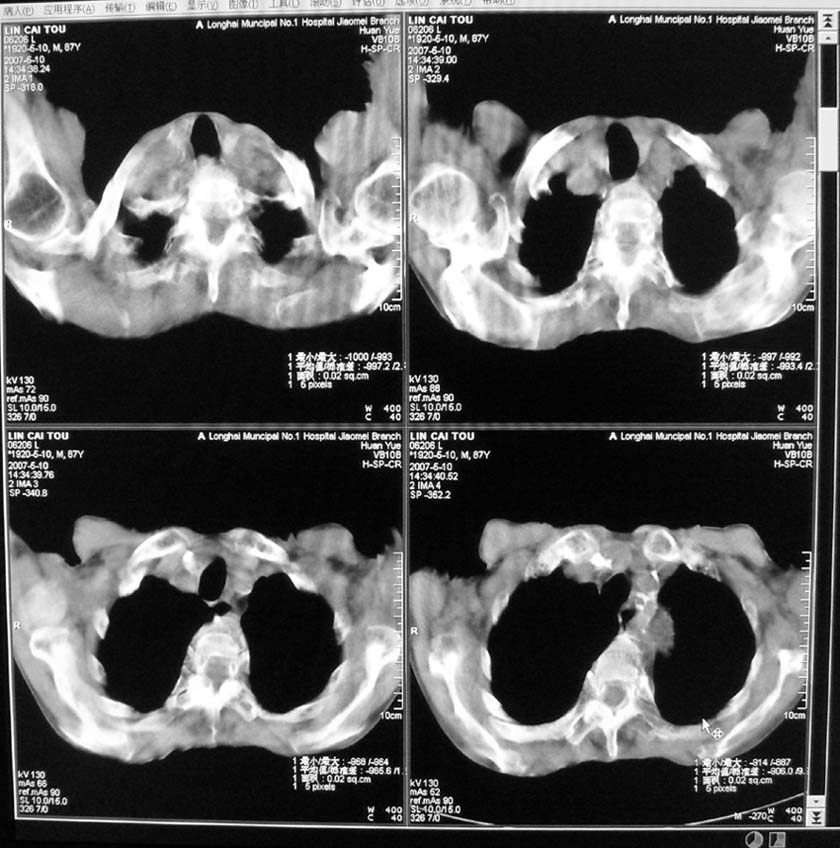

以下是引用小初学者在2007-5-12 16:26:00的发言:[br]1、心衰肺水肿两侧胸腔积液2、心包积液3、心瓣膜钙化